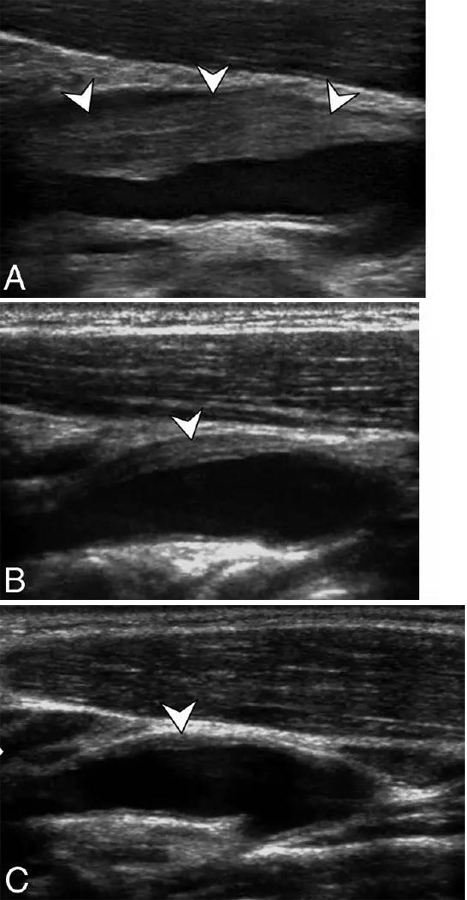

例3:下图A为首次超声,B为14天随访超声,C为6个月超声。显示颈动脉分叉处颈内动脉血管周围浸润(短箭头),14天时病变迅速减轻,6个月时仅遗留薄层异常病变。